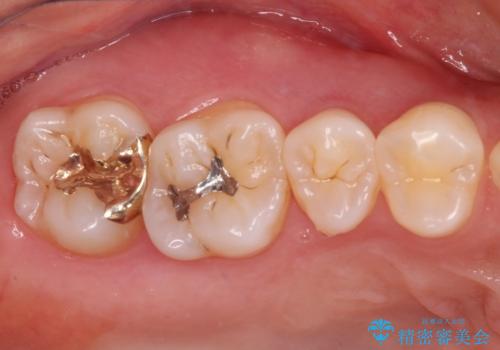

セラミックとゴールド 奥歯のむし歯治療

下顎は口を開けたときに目立つためセラミックインレーに、上顎奥歯は機能面を優先してゴールドインレーにて修復治療を行うこととしました。

機能面を優先すると、PGAインレー(ゴールドインレー)による修復治療やPGAクラウンによる補綴治療が望ましいのですが、笑ったときに見えている銀歯がどうしても気なってしまうとのことで、目立ってしまう奥歯はセラミックインレーやセラミッククラウンを装着することとしました。

見た目を気にすることなくむし歯治療を行うことができ、患者様に大変満足していただきました。